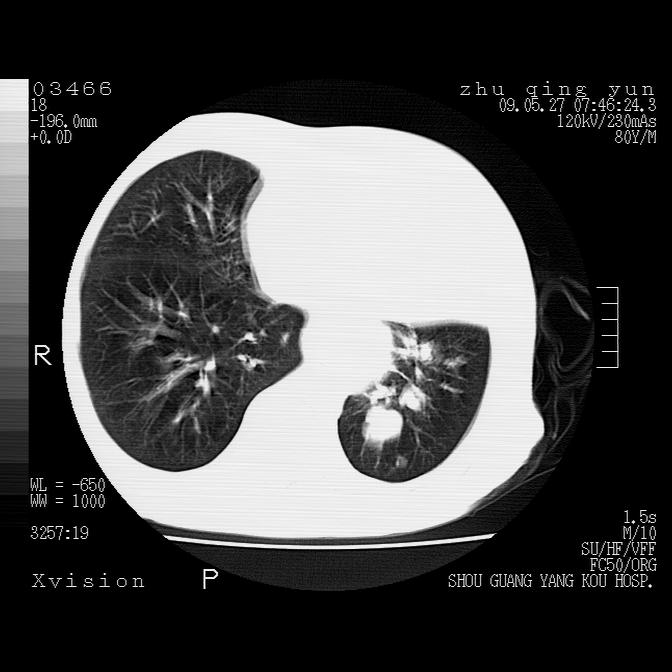

左肺下叶见多发片状及结节状病灶,左肺基底段支气管闭塞,纵隔内见多发淋巴结肿大,纵隔向左侧移位,左侧胸廓变小。应该是左肺下叶中心型肺癌,纵隔淋巴结转移,左侧肺内转移,左肺基底段肺不张,阻塞性肺炎。

1)考虑左肺中央型肺癌并左肺下叶阻塞性肺炎、不张;左胸膜腔积液、心包积液、纵隔淋巴结转移;癌肿累及左心房。2)左心室大。冠状动脉壁钙化斑。

考虑左肺中央型肺癌并左肺下叶阻塞性肺炎、不张;左胸膜腔积液、心包积液、纵隔淋巴结转移;癌肿累及左心房